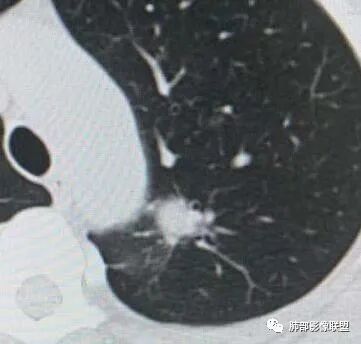

二.左肺上叶前段磨玻璃结节:

该结节较大,边界清楚,小叶间隔阻挡特征相当明显,微浸润腺癌的诊断几乎没有争议!

左肺上叶前段可见一磨玻璃结节,边界清,可见小叶间隔阻挡、毛刺 、胸膜牵拉,考虑微浸润腺癌。左肺上叶尖后段可见一实性结节影,边缘光整,光滑浅分叶,周围可见晕征,增强扫描明显延迟强化,可见血管贴边征,结节内未见气管及血管影,女性,考虑PSP

左肺上叶前段可见一磨玻璃结节,胸膜牵拉,考虑微浸润腺癌。左肺上叶尖后段可见一实性结节影,边缘光滑浅分叶,周围可见晕征,增强扫描明显延迟强化,可见血管贴边征,结节内未见气管及血管影,女性,考虑PSP。

45岁女性,无症状。CT:左上叶前段见一小磨玻璃结节,边请,似有毛刺,边缘见月芽铲,考虑AIS→MIC可能;左上叶尖后段见一圆形实性结节,边清,无分叶,见血管及支气管贴边,增强后延迟强化,考虑良性结节,PSP可能性大,稍不放心的地方局部边缘见边界清楚的磨玻璃影,注意鉴别恶性肿瘤。